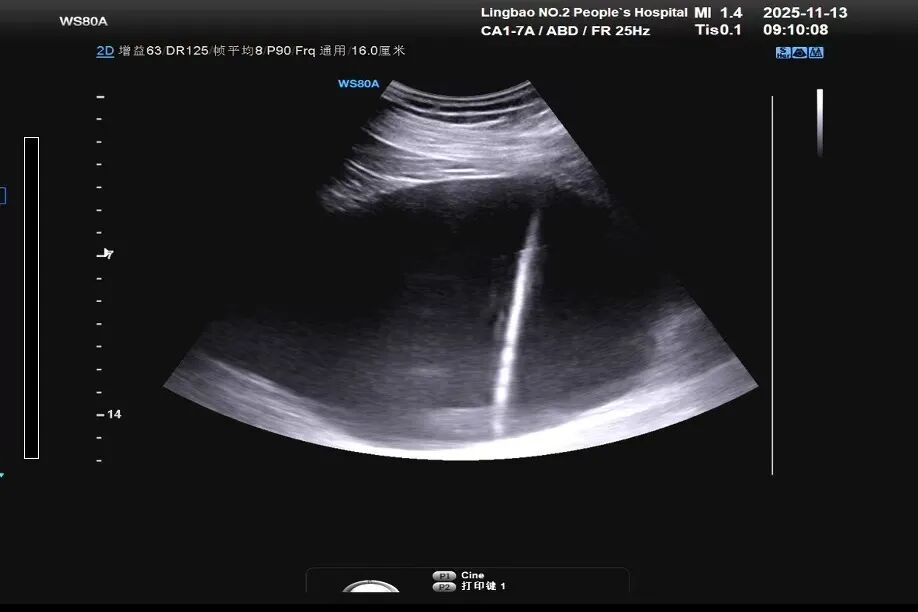

近日灵宝市二院超声科成功为一位重度肾积水患者进行超声引导下经皮肾盂造瘘术,引流效果立竿见影,患者压迫症状明显减轻,为挽救患者肾脏功能,提高生活质量创造了条件。

患者张某,男,46岁,因右侧腰背部疼痛来我院泌尿外科就诊,经CT检查后发现该患者右肾及右侧输尿管多发结石,导致右肾重度积水,右侧输尿管重度扩张。看到这个诊断结果后,泌尿外科郝波波主任高度重视,考虑到患者还很年轻,这么严重的肾积水,如果不尽快处理,会严重压迫肾实质,导致肾脏缺血、萎缩,进而导致右肾功能丧失,影响患者生活质量。泌尿外科郝波波立即与超声科毋荃梅主任进行联系,经过全面评估后,制订出最适合的穿刺方案,最终于11月13日上午成功为患者进行了超声引导下经皮右肾盂造瘘术,手术置管顺利,当场引流出淡黄色清亮尿液,患者感觉良好,腰背部胀痛的感觉明显得到缓解!